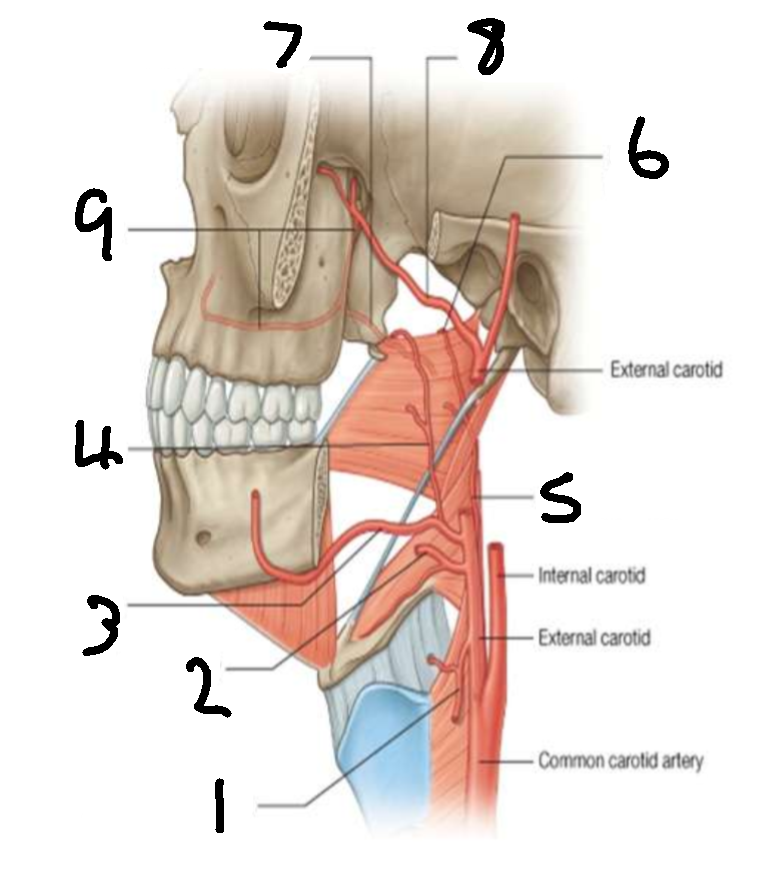

What is 1?

superior thyroid artery

What is 2?

lingual artery

What is 3?

facial artery

What is 4?

ascending palatine artery

What is 5?

ascending pharyngeal artery

What is 6?

palatine branch of pharyngeal artery

What is 7?

lesser palatine artery

What is 8?

maxillary artery

What is 9?

greater palatine artery